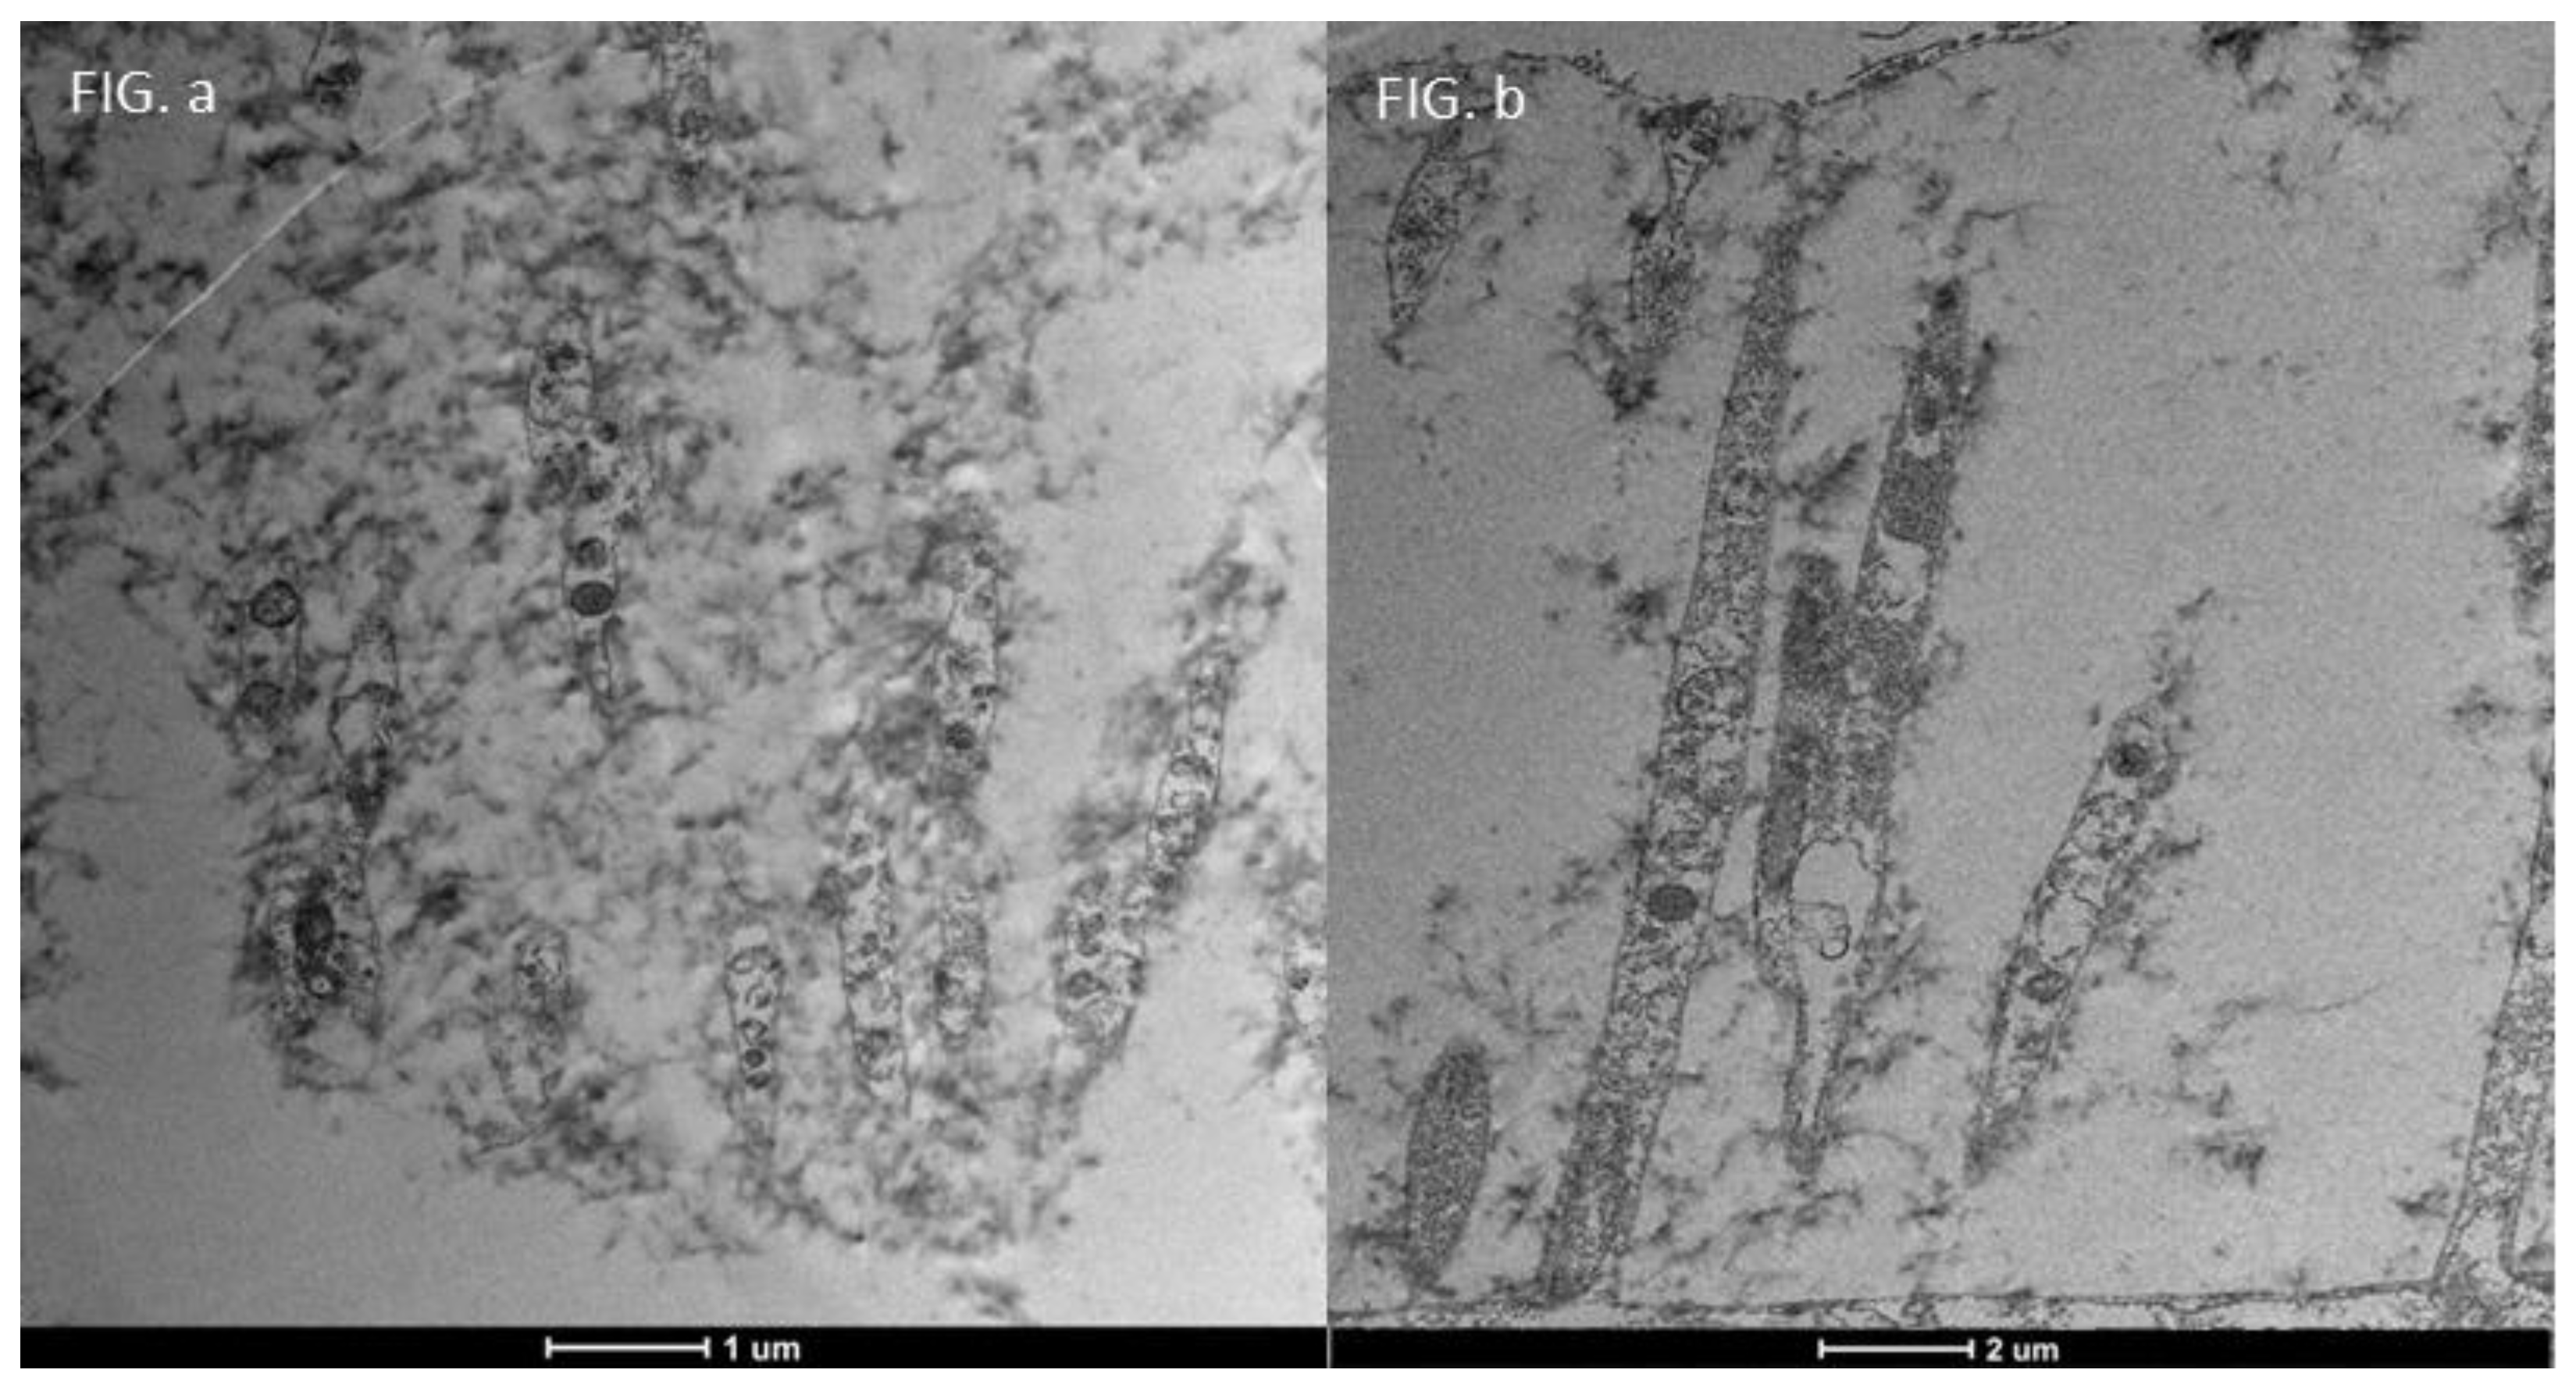

3.3. Healthy Patients (Grade 0) (Figure 12)

| TEM Evaluation Table | ||||

| Grade 0 | Grade 1 | Grade 2 | Grade 3 | Grade 4 |

| Presence of glicocalyx and presence vescicular transport | Reduction of Glicocalyx and presence of vescicular transport | Absence of glicocalyx and reduction of vescicular transport | No glicocalyx, No vescicular transport, Reduction of lenght of microvilli | flattening of the plasma membrane, absence of exchange with the outside |